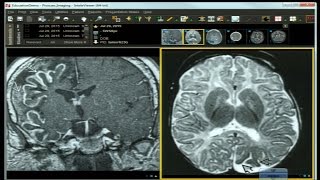

Dr. Atif Zafar, UNM, "Treating Cavernous Angioma Symptoms" Angioma Alliance National Conference 2019

Dr. Atif Zafar, Medical Director of the Angioma Alliance-recognized CCM Center of Excellence at the University of New Mexico Health System, discusses ...

Angioma Alliance